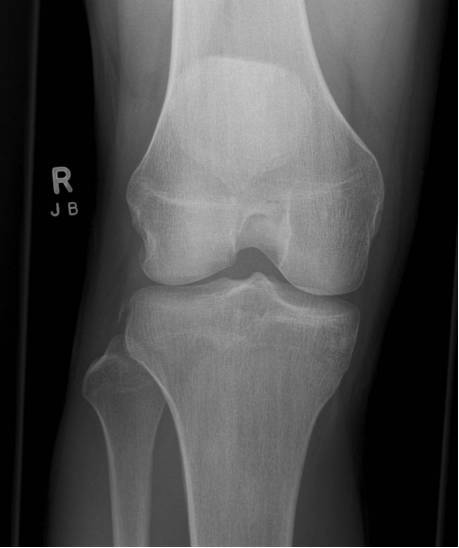

Segond骨折

胫骨平台前外侧撕脱骨折,多因为下肢过度内翻加内旋暴力所致,常伴有前交叉韧带、内外侧半月板的损伤。

反Segond骨折

胫骨平台内侧撕脱骨折,常因为下肢外翻应力加外旋所致。